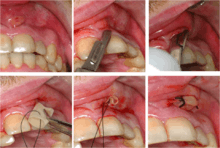

Clinical & xray correlation of pericoronitis

clinical shot of pericoronitis

An operculum (green arrow) over a partially erupted lower left third molar tooth. There is minimal inflammation and recurrent swelling.

xray of pericoronitis

A radiograph of the above tooth showing chronic pericoronitis, operculum (blue arrow) and bone destruction (red arrow) from chronic inflammation. Tooth is slightly disto-angular.

Pericoronitis is inflammation of the soft tissues surrounding the crown of a partially erupted tooth.[24] The lower wisdom tooth is the last tooth to erupt into the mouth, and is, therefore, more frequently impacted, or stuck, against the other teeth. This leaves the tooth partially erupted into the mouth, and there frequently is a flap of gum (an operculum), overlying the tooth. Bacteria and food debris accumulate beneath the operculum, which is an area that is difficult to keep clean because it is hidden and far back in the mouth. The opposing upper wisdom tooth also tends to have sharp cusps and over-erupt because it has no opposing tooth to bite into, and instead traumatizes the operculum further. Periodontitis and dental caries may develop on either the third or second molars, and chronic inflammation develops in the soft tissues. Chronic pericoronitis may not cause any pain, but an acute pericoronitis episode is often associated with pericoronal abscess formation. Typical signs and symptoms of a pericoronal abscess include severe, throbbing pain, which may radiate to adjacent areas in the head and neck,[20][25]:122 redness, swelling and tenderness of the gum over the tooth.[26]:220–222 There may be trismus (difficulty opening the mouth),[26]:220–222 facial swelling, and rubor (flushing) of the cheek that overlies the angle of the jaw.[20][25]:122 Persons typically develop pericoronitis in their late teens and early 20s,[27]:6 as this is the age that the wisdom teeth are erupting. Treatment for acute conditions includes cleaning the area under the operculum with an antiseptic solution, painkillers, and antibiotics if indicated. After the acute episode has been controlled, the definitive treatment is usually by tooth extraction or, less commonly, the soft tissue is removed (operculectomy). If the tooth is kept, good oral hygiene is required to keep the area free of debris to prevent recurrence of the infection.[20]:440–441